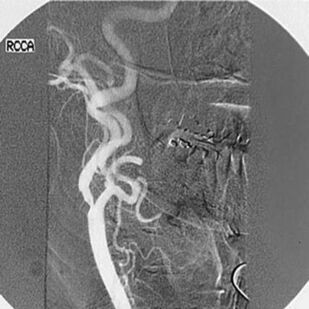

В атласе представлены более 1200 цветных иллюстраций по всем основным патологическим процессам, с которыми можно встретиться на практике, а также при изучении курса патологии или при подготовке к квалификационному экзамену по медицинским специальностям, проводимому в США (USMLE). Принцип построения атласа соответствует главам 7-го издания руководства «Основы патологии болезней Роббинса и Котрана» (Robbins and Cotran Pathologic Basis of Disease). Иллюстрации данного атласа дополняют рисунки, представленные в этом руководстве. В атлас включены иллюстрации наиболее важных рентгенологических изменений, которые отражают реальные клинические проявления при конкретных заболеваниях. Высококачественные иллюстрации имеют маркировку для определения ключевых признаков патологических изменений. В каждом наблюдении представлено комплексное описание ключевых морфологических признаков, а также клинико-лабораторные данные по наиболее важным разделам патологии. Картины макроскопических и микроскопических изменений дополнены цветными рисунками и схемами, а также соответствующими рентгенограммами. Атлас является прекрасным изданием, содержащим необходимый объём сведений или справочных материалов для читателя, имеющего различный уровень подготовки, — студента, врача, научного работника.